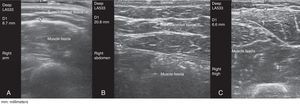

This prospective cross-sectional observational study involved 117 patients with RA (n=59) or SpA (n=58) being treated with an anti-TNF agent that the patients administered SC to themselves for a minimum of 6 months. The thickness of the ST was measured in all the patients at the sites recommended for SC injection (arms, abdomen, thighs), regardless of the preferred site for self-administration, using gray-scale ultrasound (ultrasound system equipped with a 6–18-MHz multifrequency linear transducer). Ultrasound measurement of the ST was always performed using the same method and with the patient in the sitting position. Gel was applied between the probe and the skin to avoid putting pressure on the ST with the probe (Fig. 1). The probe was placed transversely and longitudinally, on the right and left sides, at the sites recommended for SC injection. We then calculated the average between the two measurements.

The mean thickness of the ST was significantly greater in abdomen (mean±SD, 24.7±14.3mm) than in thigh (11.6±4.9mm) or in arm (9.1±4.5mm) (P<.0005).

The ST thickness may be an important factor in the selection of the needle length and injection technique,7–9 to ensure that the drug is administered to ST rather than IM tissue,8,10 which, in turn, influences the therapeutic response. High-frequency ultrasound enables direct measurements of ST thickness at any anatomical site and is harmless, easy to perform and rapid. Our results showed a significantly lower percentage of remission in the group that self-administered the anti-TNF agent in arm (n=12), with a significantly thinner ST layer (ST thickness in arm; mean±SD, 7.5±2.3mm).